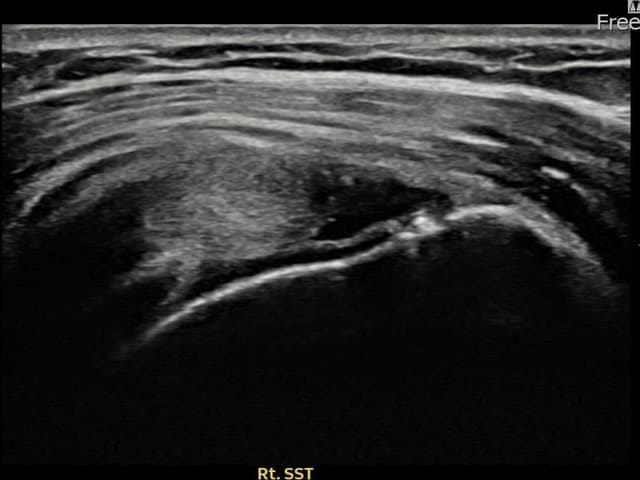

左侧 冈上肌腱 石灰化肌腱炎

9mm × 7mm